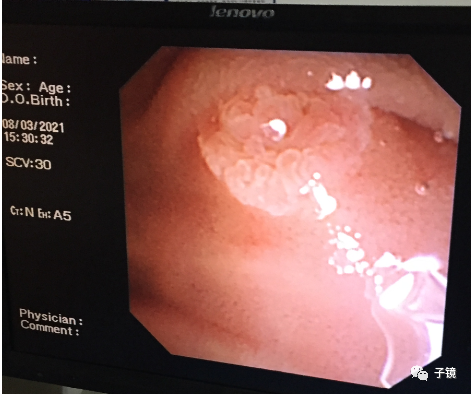

接下来进取石网篮,因为乳头开口血染,不敢贸然进网篮;于是沿导丝“生命线”进取石球囊,在胆总管上段打起来,边造影边往下拖取,感觉结石都拖至胆总管下段了,但拖取不出来。

加力往下拖,看到数个不完整的黄色碎石出来了,应该是结石给予取石球囊压碎了。